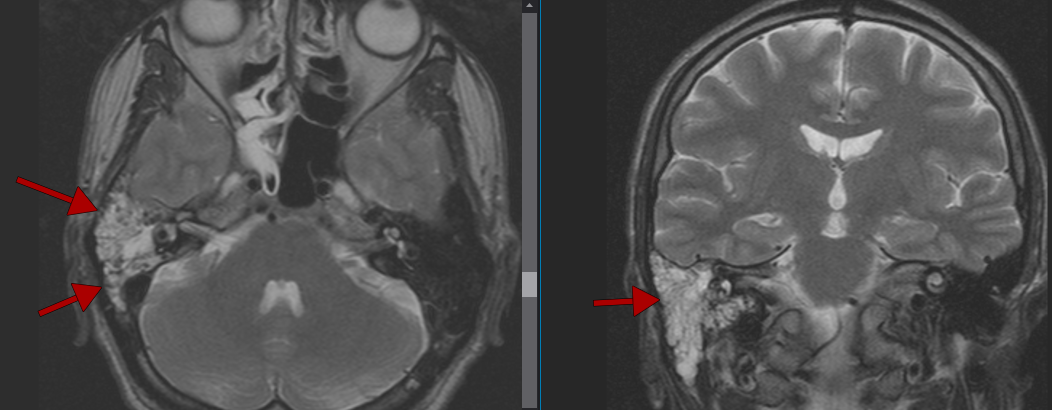

МРТ головного мозга: аксиальные срезы и анатомия